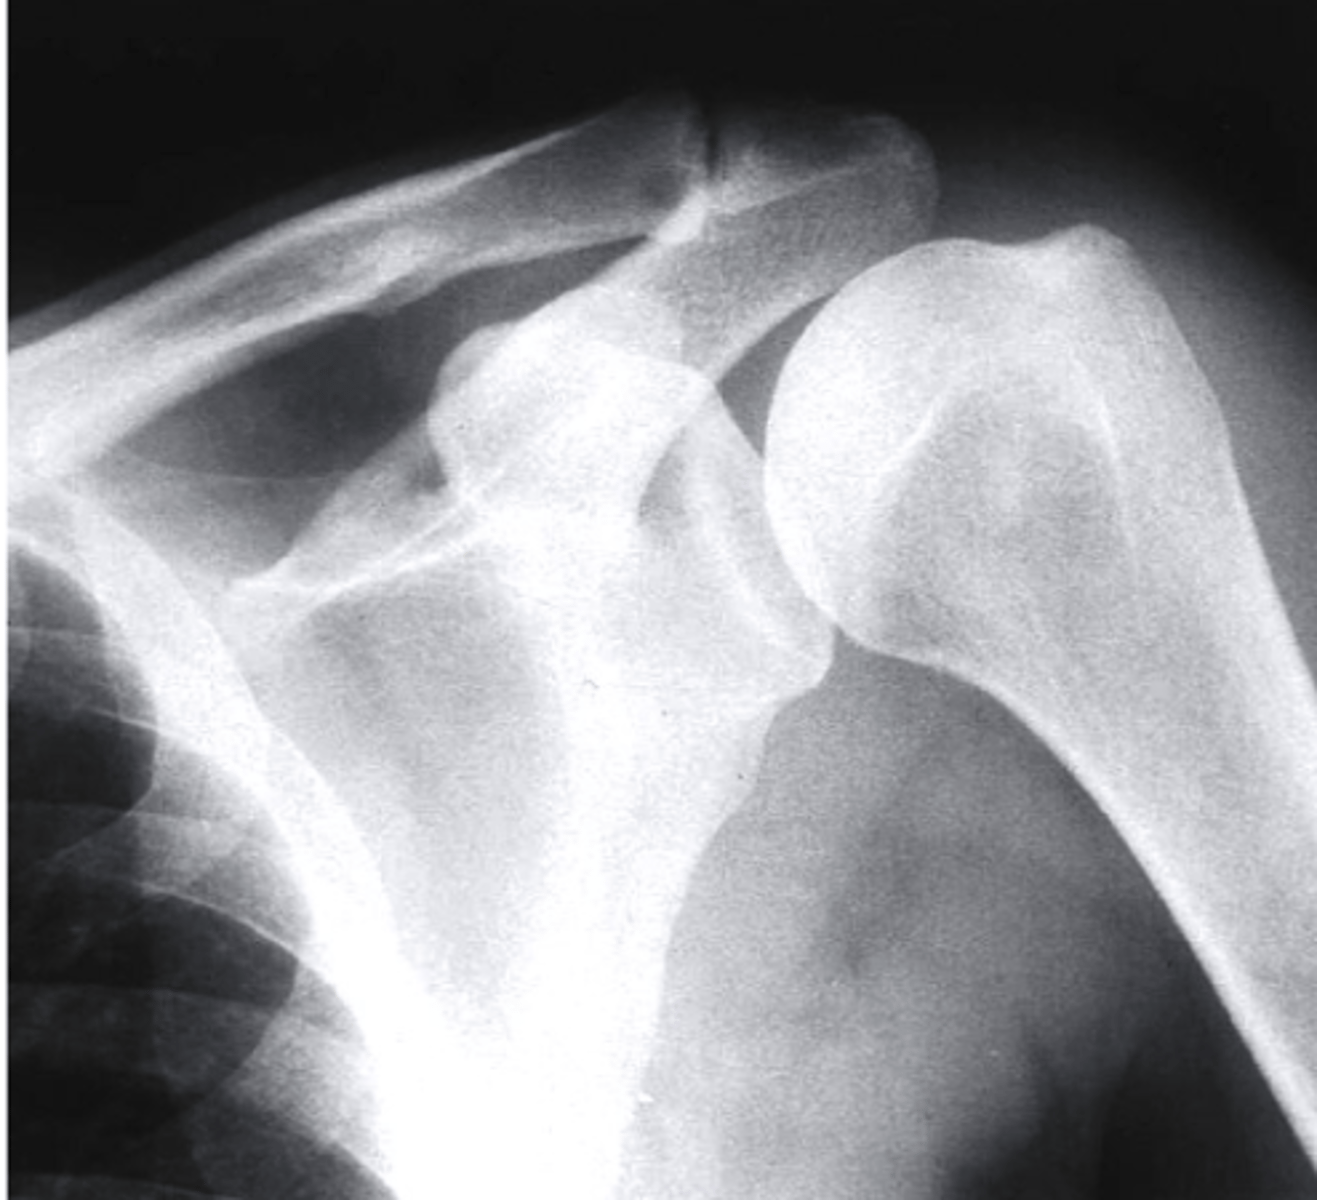

AP + ER

What view is this?